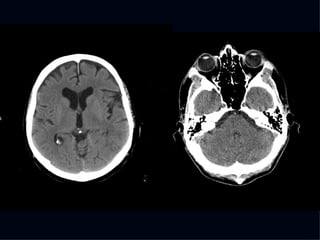

The document discusses the contributions of various figures in the field of medical imaging, including Wilhelm Röntgen and his discovery of X-rays, and the development of CT imaging and MRI technology. It highlights the historical significance of early imaging techniques and the initial skepticism from medical professionals regarding their usefulness. Key milestones in imaging are noted, along with the eventual acceptance of such technologies in clinical practice.